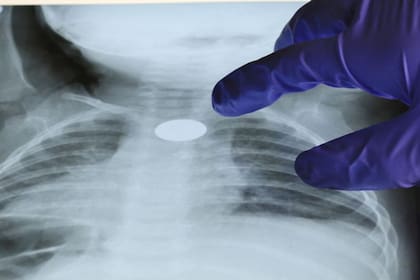

En algunas ocasiones, los objetos que inhaló un menor pueden pasar desapercibidos durante décadas. Un cartero de Preston, Inglaterra, inhaló de niño una pieza del juego Playmobil que solo fue descubierta cuando a los 47 años se sometió a un escaneo pulmonar por una tos persistente que tenía.